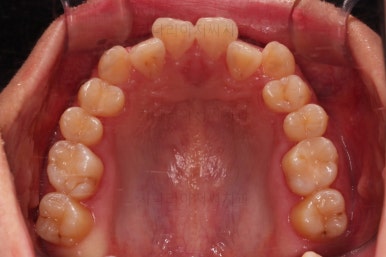

부산치아교정치과 초진 시 입안의 모습입니다.

장치를 처음 부착했고요.

이번 환자분이 선택한 장치는 윗니는 세라믹 자가결찰인 엠파워 클리어, 아래는 메탈 자가결찰인 엠파워 메탈입니다. 둘 다 같은 회사의 같은 세팅의 장치이므로 혼용이 가능하죠. 대신 비용은 좀 더 줄일 수 있습니다.